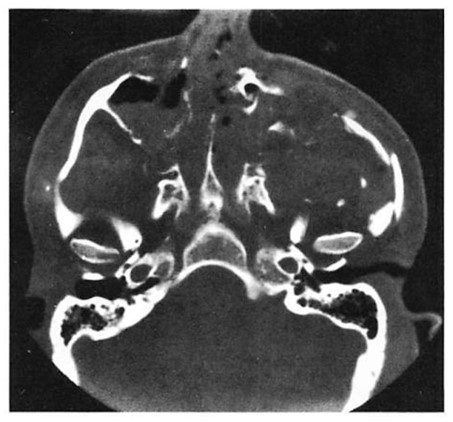

Fig 7. Very high energy Le Fort injury with open crush injury on the left side. Miniplates were used for fixation at maxillary buttresses and zygomaticofrontal sutures. Microplates were used along infraorbital rim and along the zygomatic arch on both sides. Computed tomographic (CT) scan performed 48 hours postoperatively shows loss of infraorbital rim projection on the severely comminuted left side and good projection on less severely injured right side. (A) Preoperative coronal CT shows pronounced lateral displacement of the zygoma on the left side. (B) Preoperative axial CT shows comminution and telescoping of left zygomatic arch. (C) Postoperative CT at 48 hours shows infraorbital rim and malar and arch collapse on left side.